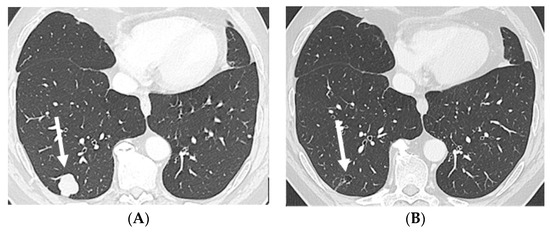

2.1. Case 1

2.2. Case 2

2.3. Case 3